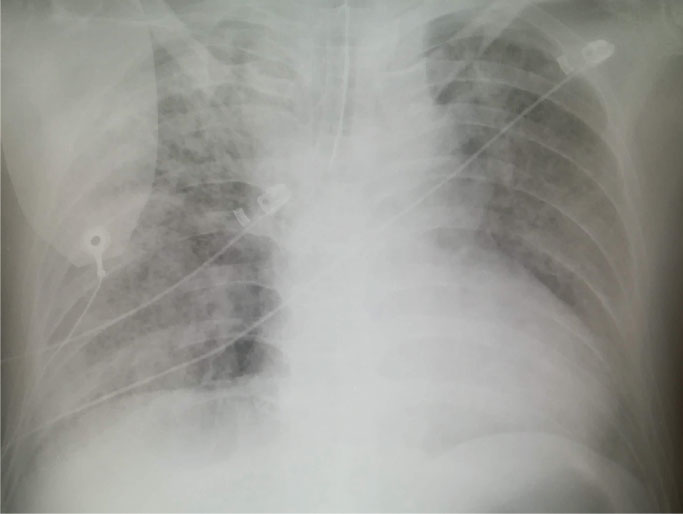

<画像所見>

・胸部レントゲン